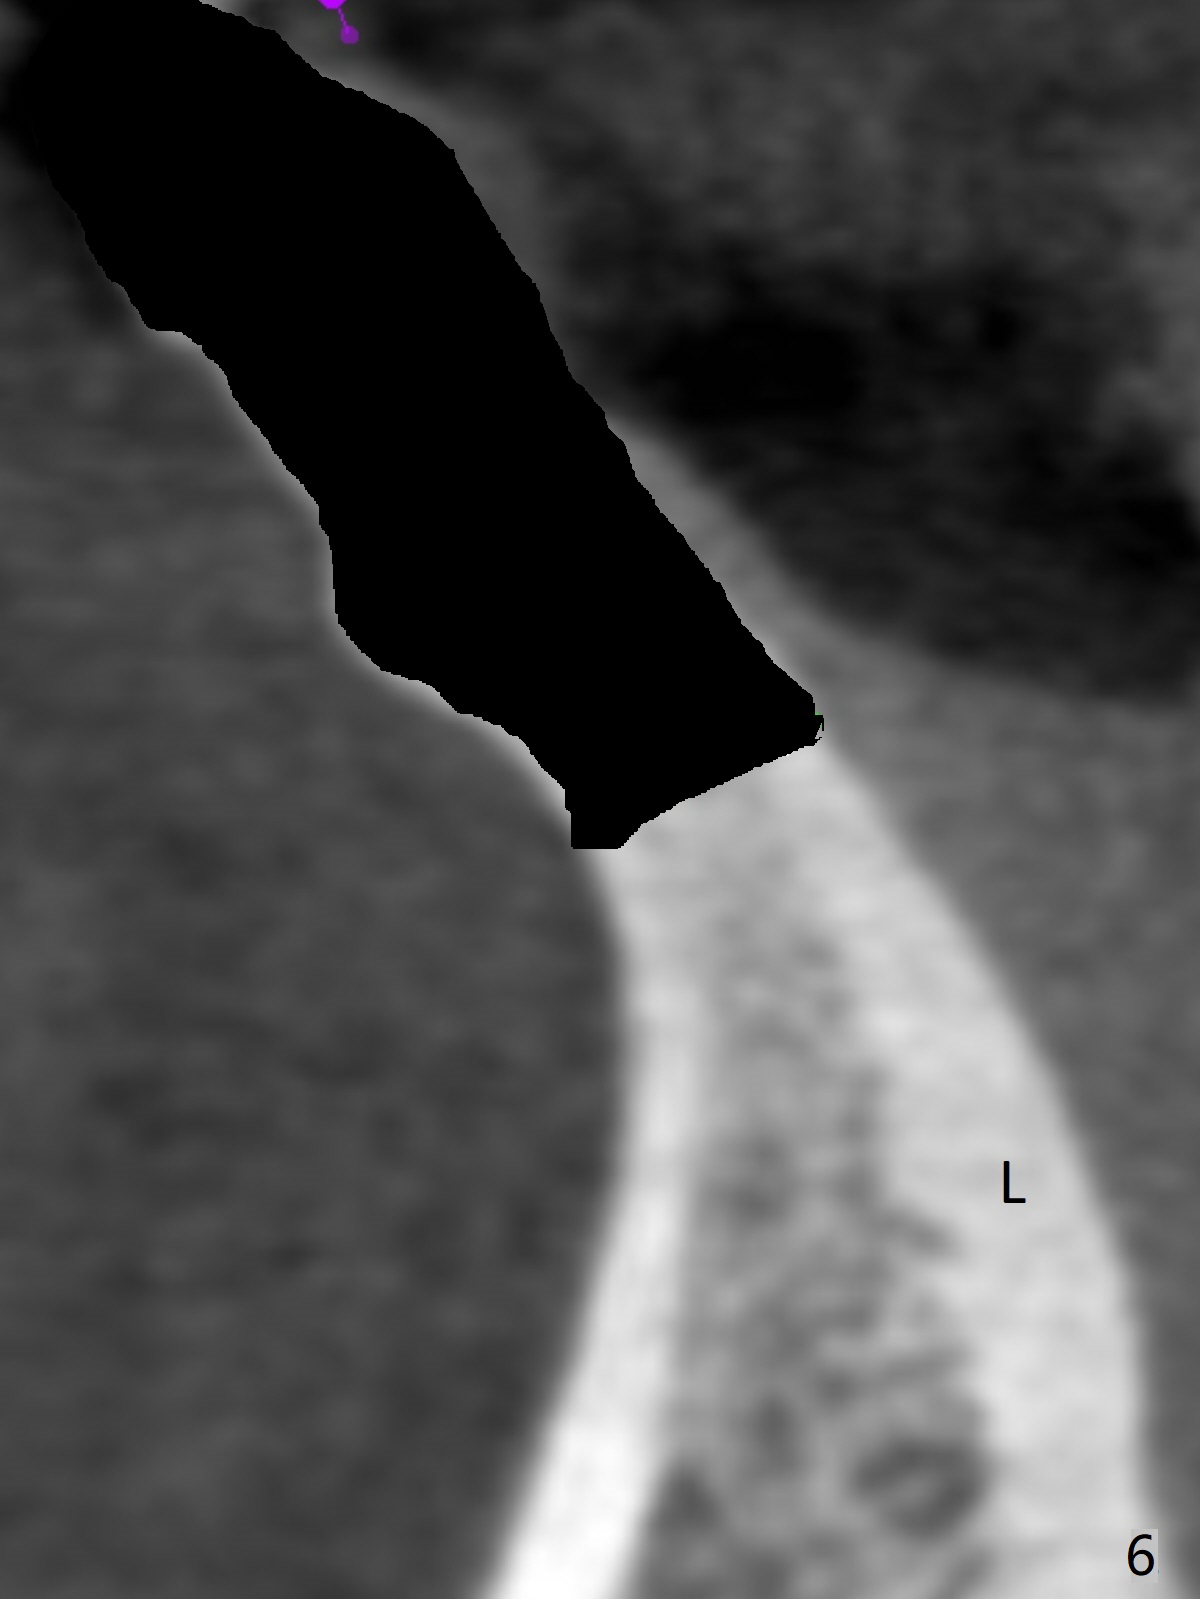

A 44-year-old woman has had bone loss at the tooth #25 for the last 4 years (Fig.1 *). Since the bone is narrow buccolingually (Fig.2 (CT coronal section)), a 1-piece implant with 2.5 mm in diameter is proper (Fig.3); but 12 mm in length makes the implant close to the lingual plate (Fig.2-4 L), with possible perforation. To avoid the latter, a shorter implant seems more appropriate for the site (Fig.5). Osteotomy is initiated in the apex with two fingers holding the buccolingual plates. Take PA preop. There is no buccal or lingual plate when the tooth is extracted; the socket bottom is flat buccolingually (Fig.6).